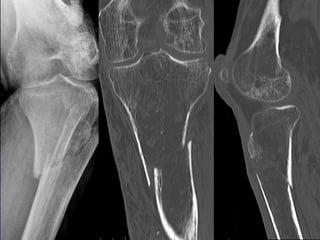

HIP FRACTURES